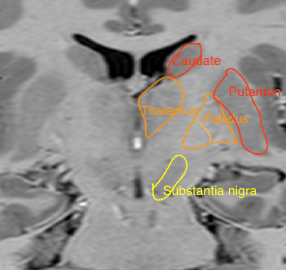

Figure 3. Coronal inversion recovery image at the level of the foramen of Monro. The difference in signal intensity between the diencephalic (thalamus and pallidus) and telencephalic structures (caudate nucleus and putamen) is visible. The thalamus is located as cranial as the insular cortex.

Because of their role in the motor control system, the subthalamic nucleus and the substantia nigra rostrally in the midbrain are often included when referring to the basal ganglia.